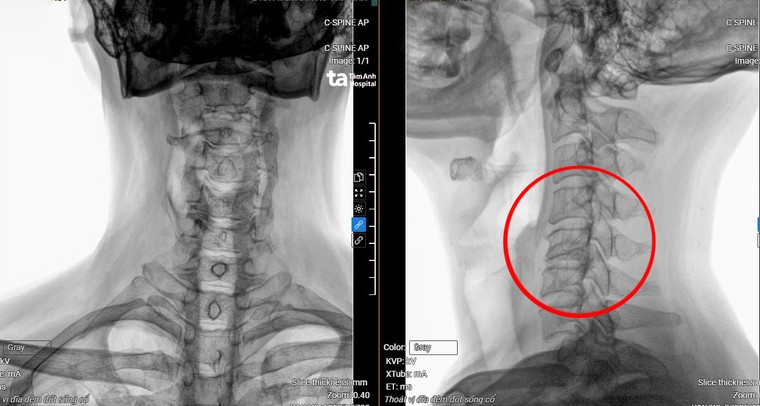

ThS.BS.CKI Vũ Đức Thắng, khoa Cột sống Trung tâm chấn thương chỉnh hình Bệnh viện Đa khoa Tâm Anh TP Hồ Chí Minh cho biết, qua kết quả chụp MRI 3 Tesla cho thấy bệnh nhân An bị thoát vị đĩa đệm cột sống cổ nặng từ C3 đến C7, gù cột sống cổ, chèn ép làm tổn thương tủy C5, C6 (vị trí đốt sống cổ thứ 5 và thứ 6).Ngoài ra, cột sống thắt lưng của anh cũng bị thoát vị và chèn ép thần kinh khá nặng ở tầng L4, L5 (vị trí đốt sống lưng thứ 4 và thứ 5).

| Phim chụp MRI hiển thị vị trí đốt sống cổ bị thoát vị, tổn thương tủy. Ảnh: BV |